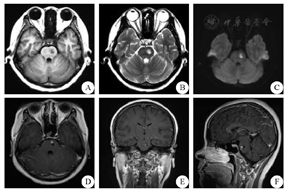

女性,25岁,因"发热20余天,突发右侧肢体无力4 d"于2014年7月9日由首都医科大学附属北京朝阳医院神经内科收治入院。患者入院前20 d受凉后出现发热,最高体温38.8 ℃,伴咳嗽,咳嗽时伴头痛,给予口服感冒药略有好转;入院4 d前安静状态下突发右侧肢体无力,行走轻度乏力,右手持物不稳,无言语不利,头部CT提示"左侧脑桥低密度灶"。近1月体质量下降5 kg。既往体健,父亲19岁时患有结核性胸膜炎病史。入院体检:血压118/55 mmHg(1 mmHg=0.133 kPa)。化验检查:(1)血常规、凝血功能、肝炎、自身抗体、体液免疫、髓过氧化物酶、蛋白酶、自身免疫缺陷病毒、梅毒、肿瘤标记物、甲状腺功能等均正常;(2)生化:C反应蛋白1.10 mg/dL(↑),动态红细胞沉降率25 mm/h(↑),总胆固醇3.06 mmol/L(↓),高密度脂蛋白胆固醇0.77 mmol/L(↓),低密度脂蛋白胆固醇1.40 mmol/L(↓),甘油三脂2.95 mmol/L(↑),余生化全项大致正常;(3)脑脊液:初压120 mmH2O(1 mmH2O=0.0098 kPa),无色透明,潘氏试验阴性,白细胞53/nL,红细胞1/nL,单核73.6%,多核26.4%,糖1.9 mmol/L(↓),氯化物121.8 mmol/L,蛋白46 mg/dL(↑),腺苷脱氨酶3 U/L,脑脊液病原学阴性;(4)血结核杆菌抗体试验阳性,血肺炎支原体抗体IgM阳性,血肺炎衣原体抗体IgM阳性;血混合淋巴细胞培养+干扰素检测A:>1000 SFCs/106,血混合淋巴细胞培养+干扰素检测B:164 SFCs/106,血真菌-β-D葡萄糖<10 pg/mL,血降钙素原0.11 ng/mL。影像学检查:(1)头颅MRI :左侧桥脑呈现异常高信号改变,增强序列可见明显强化病灶(图1)。(2)头部MRA和颈部CTA:未见明显异常。(3)胸部CT:双肺粟粒样结节及沿支气管血管束分布稍大结节,考虑结核血行播散合并气道播散;T10椎体骨质局限性低密度灶,考虑胸椎结核(图2)。(4)支气管镜检查:左肺尖后端支气管镜活检提示支气管黏膜慢性炎症;石蜡切片提示典型分支杆菌阴性,结核杆菌临界阳性。

A:头MRI平扫:轴状位T1WI序列;B:头MRI平扫:轴状位T2WI序列;C:头MRI平扫:轴状位弥散加权成像序列;D:头MRI平扫+增强:轴状位T1WI增强序列;E:头MRI平扫+增强:冠状位T1WI增强序列;F:头MRI平扫+增强:矢状位T1WI增强序列